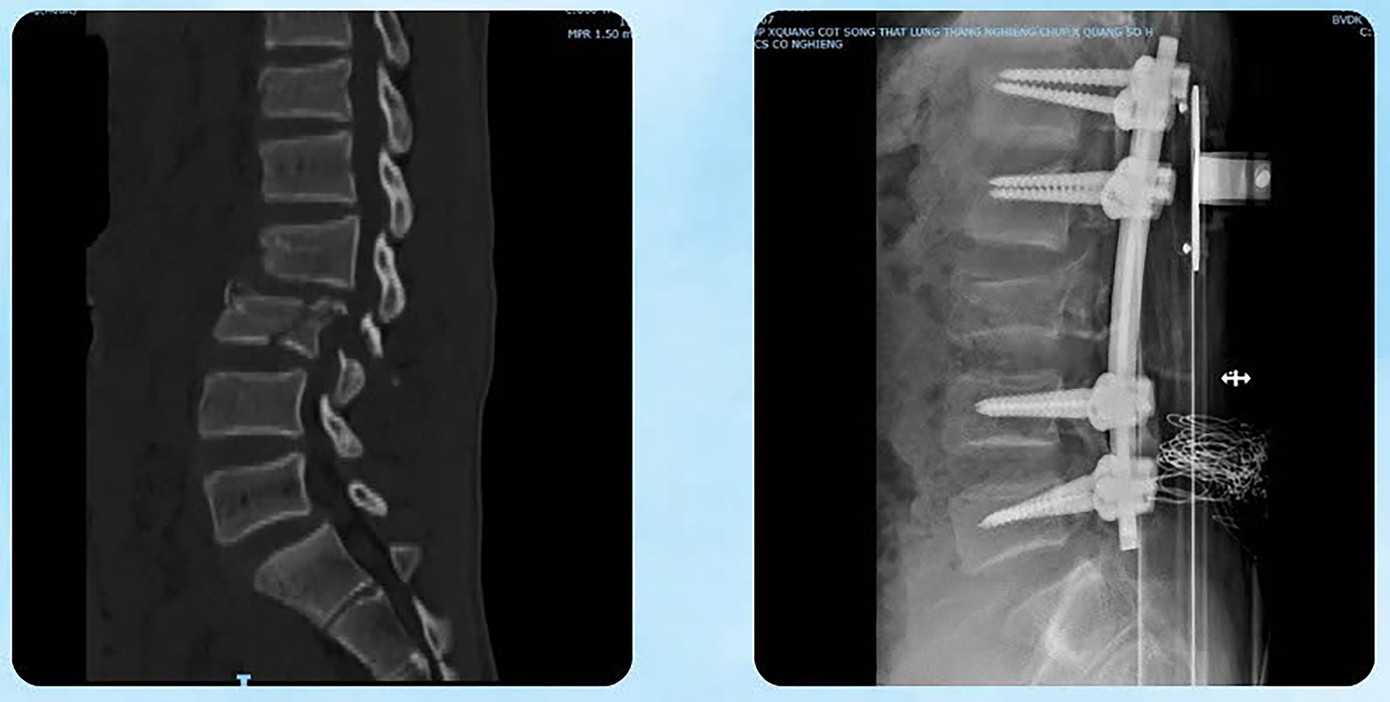

Đặc biệt, bệnh nhân bị gãy trật cột sống đoạn L2–L3, tụ máu ngoài màng tủy, tủy dập và rách màng tủy – những thương tổn có thể để lại di chứng rất nặng nề.

Bệnh nhân được phẫu thuật cắt lọc, khâu phục hồi đại tràng ngang, xử lý dịch máu ổ bụng; phẫu thuật cột sống lối sau để nắn trật đoạn L2–L3, cố định bằng hệ thống nẹp vít dưới hướng dẫn C-arm; cắt bản sống, lấy máu tụ ngoài màng tủy giải ép tủy và vá màng tủy bị rách. Ngoài ra, bệnh nhân còn được kết hợp xương đùi bằng nẹp vít khóa qua đường mổ nhỏ.